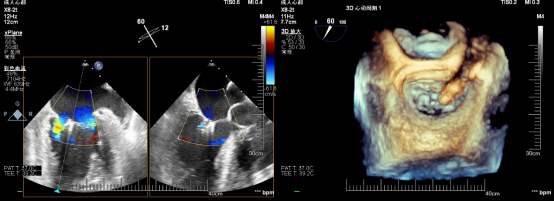

在患者全麻状态下经股静脉置管、经食道超声(TEE)引导房间隔穿刺后置入导引鞘管,手术团队将夹合器精准送达二尖瓣反流区。在TEE及X线引导下,手术团队利用二尖瓣夹(Mitraclip)准确捕获二尖瓣叶,试夹闭后经过超声证实夹闭有效,释放成型夹。术后超声评估,二尖瓣口仅见轻微反流,反流情况明显改善,患者各项生理指标正常,Mitraclip手术高质量完成。患者于术后第3天顺利出院,出院前检查患者二尖瓣反流各项参数指标恢复都超出了预期效果。

术后心超